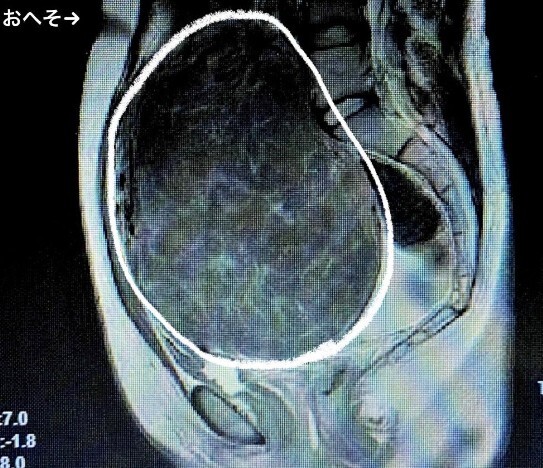

1Google画像で出て来た画像をお借りしました。一番似てる画像です。私もこの方と同じ状態で重さとしては3〜4キロ。1月に手術日程が決まりました。その前に生理を止める薬を飲まなければいけないので準備に時間がかかります。大腸検査して欲しくて行ったのに…😢#子宮全摘出 pic.x.com/JiaUmgbAV3 x.com/onoda_kimi/sta…